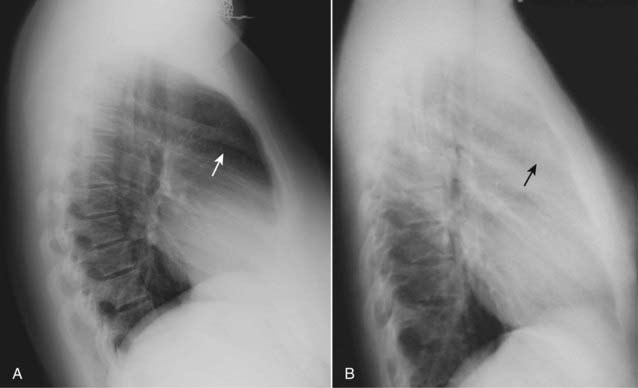

image

Figure 2-3 The spine sign.

Frontal (A) and lateral (B) views of the chest demonstrate airspace disease on the lateral film (B) in the left lower lobe that may not be immediately apparent on the frontal film (look closely at A and you may see the pneumonia in the left lower lobe behind the heart). Normally, the thoracic spine appears to get “blacker” as you view it from the neck to the diaphragm because there is less dense tissue for the x-ray beam to traverse just above the diaphragm than in the region of the shoulder girdle (see also Fig. 2-2). In this case, a left lower lobe pneumonia superimposed on the lower spine in the lateral view (solid white arrow) makes the spine appear “whiter” (more dense) just above the diaphragm. This is called the spine sign. Note that on a well-positioned lateral projection, the right and left posterior ribs almost superimpose on each other (solid black arrow), a sign of a true lateral.